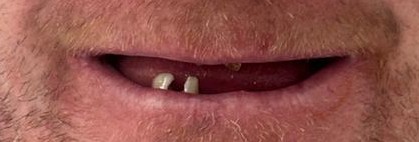

After

When the patient saw his fixed teeth, he became emotional. After living for so long without proper teeth and not feeling able to smile, the change had a deep personal impact.

He was especially happy that the treatment gave him a smile he felt proud of again.

The treatment achieved a wonderful outcome for the patient, including:

• fixed teeth

• improved chewing

• restored smile confidence

• better comfort

• long-term stability

• improved quality of life